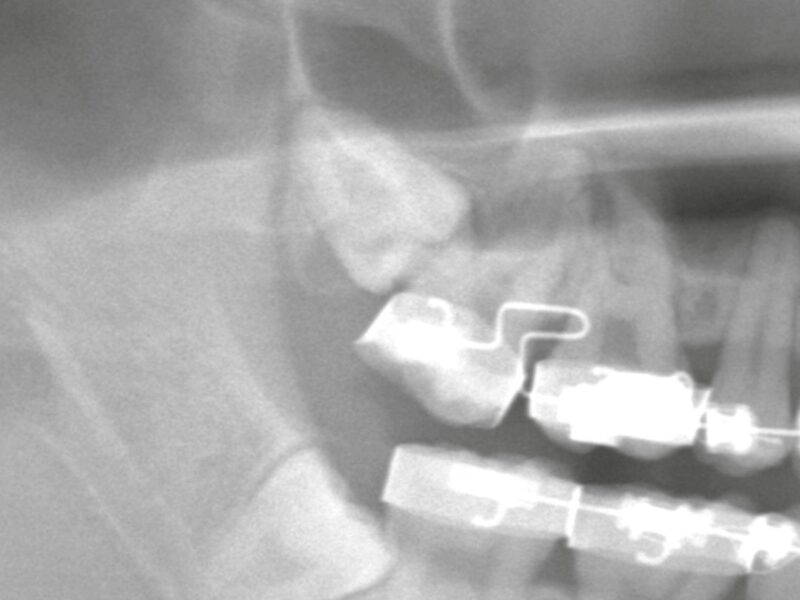

症例紹介

親知らずの抜歯や顎関節症の治療では、患者様の不安や症状にしっかり寄り添いながら、安心・安全な治療を提供しています。

「難しいと言われた親知らず」「顎の不調が治らない」などのお悩みは、ぜひ一度、当院へご相談ください。